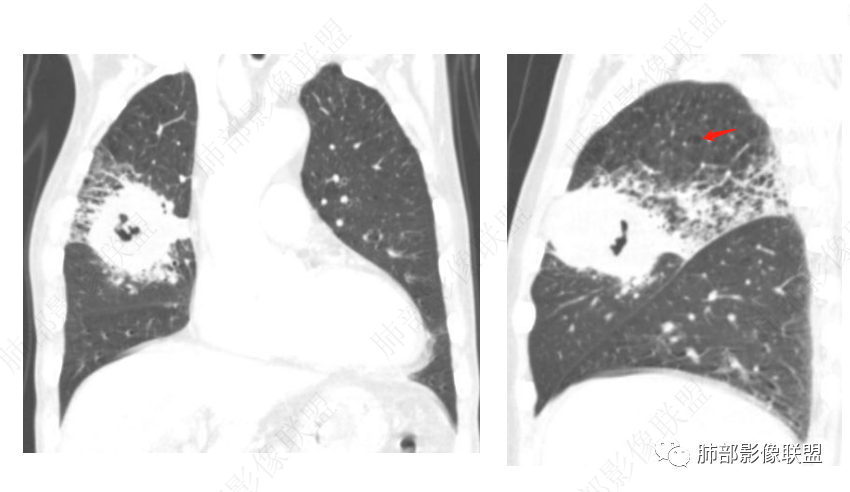

右肺上叶实变,密度不均,内可见小气液平,周磨玻璃影,斜裂稍内凹,右下肺可见斑片影,强化可见血管走行自如,右侧胸腔少量积液,考虑感染性病变,努卡?放线菌?

右上肺大片状实变,邻近肺野网格状间质改变,实变内见低密度坏死及悬浮气泡,实变内见多发环强化,血管影走行自然,急性病程,炎性标志物升高,首先考虑感染性病变,放线菌肺炎或TB可能性大,右上肺间质病变并大片实变,诊断思路要高度考虑有否併发恶性占位的可能,鉴别一下腺癌

男,70,反复乏力、纳差20天,发热1天。胸部CT:肺气肿背景,右肺上叶中叶大团片影,实变十磨玻璃渗出。增强实性斑片影内密度不均,可见多发低密度坏死及不规则空洞影,空洞内壁尚光滑,血管边缘模糊。支气管管壁增厚,管腔通畅。右下叶可见小片渗出影。考虑支气管肺炎进展?病原考虑能形成肉芽肿、坏死空洞的微生物,TB?奴卡?鉴别鳞癌。

老年男性,乏力纳差,进食量明显下降,发热,后期少许黄脓痰,无咯血。无胸痛。未提口腔卫生情况,发热时间段不明确,肺气肿背景,气管内痰拴还是其他?觉得是外朝内进展病灶,右肺多叶段病灶,支气管通畅,支气管壁弥漫增厚,实变病灶内有坏死,坏死边界比较清晰,血管破坏不明显,周围散在磨玻璃,边界模糊,无树芽,实变内可疑小钙化,右侧胸水,肺门纵隔淋巴结无明显肿大。病史不太支持化脓菌感染,真菌里隐球强化不太支持,结核需要排除,厌氧菌感染带排,冠状位矢状位病灶觉得类圆形,临床肿瘤也是不能轻易排除的

发热,炎性指标高。右肺上叶实变影,凝固型坏死,裂隙状空洞,有钙化,有间质结节,考虑感染性病变,TB可能,鉴别肺炎性肺癌。

上肺优势;3是血管侵袭

2呈现奴卡之角

两个病灶独立,又有关联性,内侧病灶近端的支气管包绕在外侧病灶之中,但是走形自然

无堵塞迹象,支气管壁弥漫增厚

内部大片坏死区,其中还有不规则空洞

坏死腔内壁清,有强化环

肺动脉在实变区走形自然,坏死腔周围受压推移,走形自然,坏死区内破坏

这类坏死区内空洞,提示坏死液比较粘稠

不是液化坏死,液化坏死,这么大,有气体进来按理会形成液气平面

凝固性坏死

结核,大病灶可以符合,就是周围大片GGO,而无树芽征,不踏实啊

上叶前段病变,中叶外侧段受侵。依据南大思路,感染病变更容易跨叶?是不是更支持感染

炎性多见,而且要警惕放线菌

炎性标志物升高,有悬浮气泡,是耍首先考虑放线菌